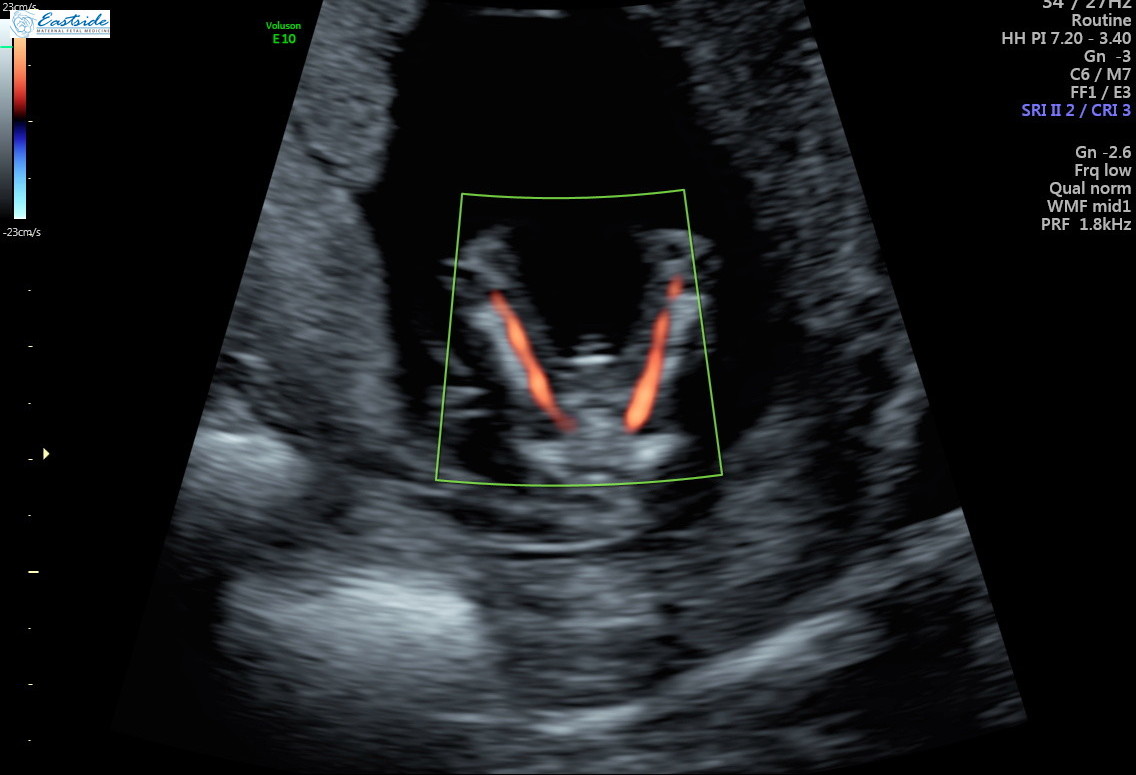

I am wondering if any experts or experienced could review the pics from my 13 week ultrasound? The tech said she was 80% sure of gender, but is it obvious to any of you? We have 3 girls so as you might guess, we are a bit anxious to find out!

Thanks! Attachment 38878Attachment 38879Attachment 38880Attachment 38881Attachment 38882Attachment 38883